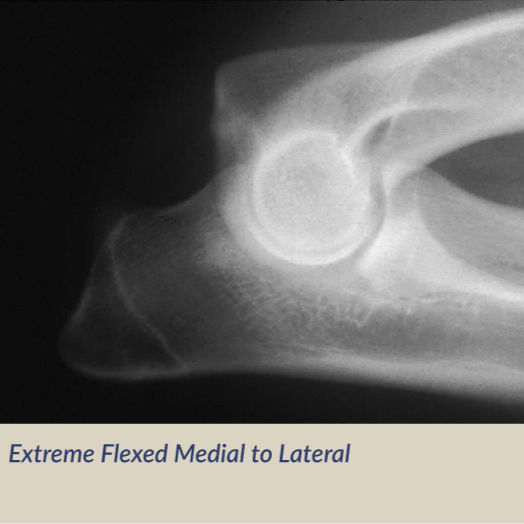

肘関節形成不全(Elbow Dysplasia)